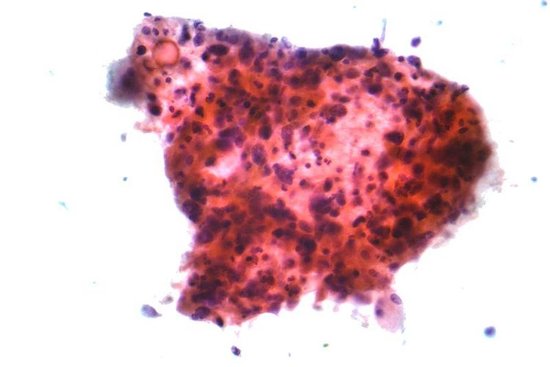

据了解,研究人员研制这种化学药物最开始的初衷是为了降低乳腺癌的再发率,但在研究的过程中,研究人员却意外的发现这种药物同时还具有其他的功效。因为,那些吞服了这种药物的人们与服用普通控制药物的人们相比,前者患上结肠癌、前列腺癌、肺癌的概率有了明显的降低。

研究人员在实验中选择了一些经基因测试或医疗审定后,被断定为有患上乳腺癌危险的女性,并将其分为两组,一组吞服控制性药物,另一组吞服了“E-75”药物。研究结果显示,吞服“E-75”药物的研究对象的乳腺癌再发率仅有10%,而吞服控制药物的一组竟高达20%。这就意味着超级抗癌药物“E-75”具有着正面积极的保护作用。研究人员之所以会选择这样的研究方法,是因为避免出现类似人们在感染流感后再注射流感疫苗的现象。

研究人员解释说,抗癌药物“E-75”的“工作方式”相对来说较为简单,它能够成功的在人们体内建立一个特有的免疫系统,这种系统能够搜寻、识别以及确认呈现在多种类型癌细胞表面的蛋白质,从而对应的进行免疫。但是并不是所有肿瘤都是由分泌这种蛋白质分子的细胞组成的,这也是为何抗癌药物“E-75”不能治疗目前所有癌症类型的主要原因。而且,抗癌药物“E-75”在人体内所建立的特有免疫系统不能击败所有癌症细胞的主要原因之一,还因为有一些癌细胞具有“欺骗”免疫系统的功能,以至于当免疫系统进行识别时,会把这些癌细胞误认为是人体的一部分。但是一旦免疫系统“揭穿”这些癌细胞的“伪装面具”,它们就会毫不留情的对这些癌细胞进行消灭,不留任何一个“活口”。